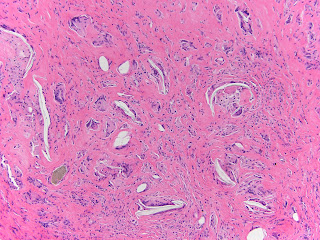

Because of a high index of suspicion, he had a single stage revision with postoperative intravenous antibiotic therapy. His cultures for Propionibacterium showed no growth; permanent sections showed a foreign body giant cell reaction with particulate debris on non-polarized and polarized microscopy as shown below.